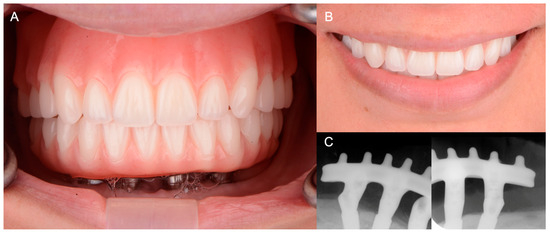

3. Results